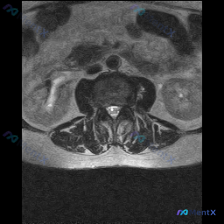

今天整理了一份只有单张腰椎MRI T2加权轴位片的椎间盘病变分析案例,跟大家分享一下读片和临床分析的思路。 病例影像基本信息 本次仅提供单张腰椎MRI T2加权轴位图像,具体读片发现如下: 1. 节段定位:根据椎体、椎弓根和关节突形态判断,该切面位于腰椎,最可能为L4/5或L5/S1水平 2. 椎间...

收到一份腰椎MRI单张轴位片,临床怀疑椎间盘病变,整理一下读片思路和分析,和大家交流。 一、影像基本信息 这是一张腰椎MRI T2加权轴位扫描图像,我们逐层拆解结构: 1. 椎体与终板:椎体后缘信号正常,低信号符合皮质骨表现,没有明显骨质破坏、水肿,也没有典型Modic终板炎改变 2. 椎间盘:髓核...